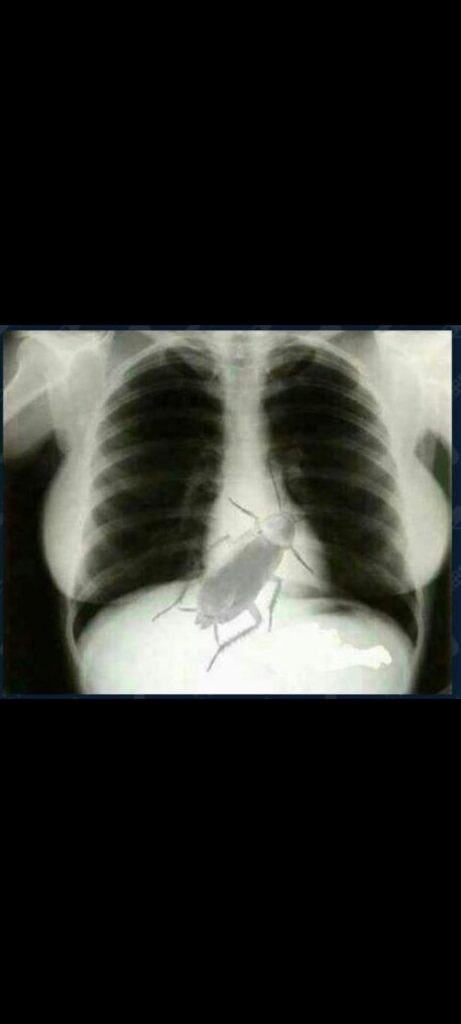

छाती में ज़िंदा कॉकरोच

यह सिर्फ एक वायरल खबर नहीं, बल्कि इंसानी ज़िंदगी से खिलवाड़ की खुली मिसाल है। केन्या/Kenya में एक मरीज को एक्स-रे दिखाकर डराया गया कि उसकी छाती में ज़िंदा कॉकरोच है। बिना दोबारा जांच, बिना किसी सीनियर कन्फर्मेशन — सीधा फैसला सुना दिया गया। क्या अब अस्पताल डर फैलाने की फैक्ट्री बन चुके हैं?

हद तो तब हो गई जब मरीज को इलाज के नाम पर सिंगापुर /Singapore भेज दिया गया। वहां सही जांच हुई तो सच्चाई सामने आई — कीड़ा मरीज के शरीर में था ही नहीं, बल्कि एक्स-रे मशीन के अंदर फंसा हुआ था! यानी गंदी मशीन, लापरवाह स्टाफ और भुगतना पड़ा मरीज को। यह गलती नहीं, सीधा अपराध है।